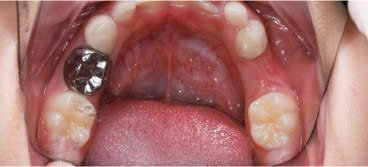

SSC (Stainless Steel Crown) là mão răng bằng thép không gỉ, được thiết kế sẵn với nhiều kích cỡ khác nhau, thường dùng để phục hồi răng sữa đã bị sâu lớn hoặc tổn thương nặng. Đây là một dạng phục hình toàn phần bao phủ toàn bộ thân răng, giúp bảo tồn và duy trì chức năng của răng sữa cho đến khi thay răng vĩnh viễn.

- Tỉ lệ thành công cao

Nhiều nghiên cứu cho thấy mão SSC có tỉ lệ tồn tại và bảo tồn răng sữa cao hơn hẳn so với trám thông thường, đặc biệt trong các trường hợp sâu răng nhiều mặt.

So với những vật liệu thông thường khác, mão thép có sẵn có nhiều ưu điểm để phục hồi răng cối sữa như:

- Bảo vệ và nâng đỡ được múi còn lại của răng

- Phục hồi lại được hình dáng của thân răng được dễ dàng

- Diện tiếp xúc với các răng bên tốt tránh được hiện tượng dắt thức ăn rất phiền toái cho trẻ